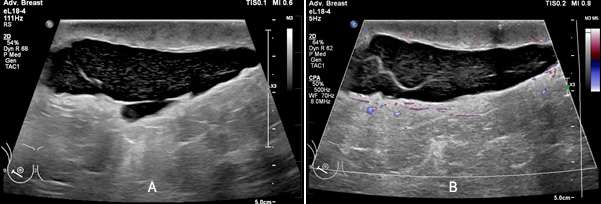

Figure 4: Compared to the patient’s prior images (A and B), images C and D demonstrate ill-defined region of increased density (red circle) adjacent to a newly placed biopsy marker with gas (radiolucent foci) following a vacuum-assisted biopsy. This is favored to represent a small hematoma at the site of biopsy.

On mammogram, hematomas appear similar to other fluid collections and most commonly appear as a well-defined mass or region of increased density. Borders may be well circumscribed or ill-defined depending on acuity of the hematoma and the integrity of the surrounding tissue. In areas of chronic hematoma, small calcium deposits may develop and evolve into areas of fat necrosis. Similar to seromas, during compression a hematoma may change in shape on mammograms.